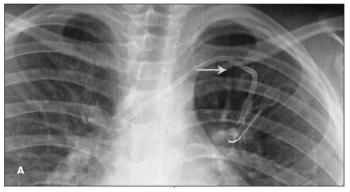

The imaging studies shown are from 2 children with cancer who underwent placement of 9.6 French left subclavian central venous catheters (CVCs) to facilitate treatment. Fracture of the catheters with subsequent embolization of the distal fragment to the pulmonary arteries was noted at about 18 months after placement. Findings suggestive of impending fracture were missed in previous radiographs. In both cases, an interventional radiologist removed the fragment via percutaneous catheterization of the right femoral vein.